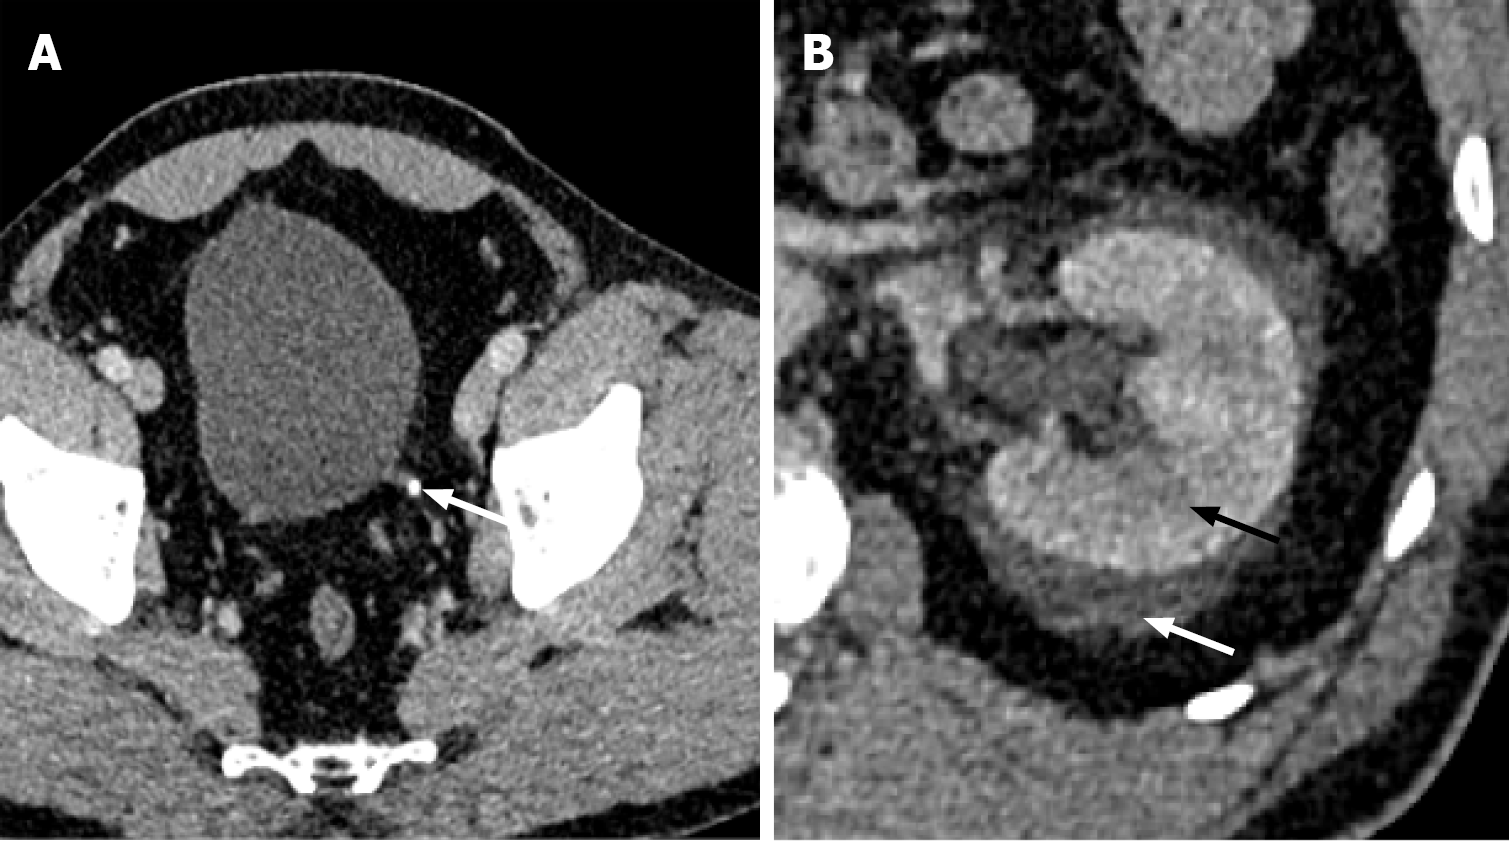

Figure 14 Xanthogranulomatous pyelonephritis.

A and B: Axial (A) and coronal (B) computed tomography demonstrating diffusely dilated renal calyceal system with renal cortical thinning (bear paw sign) (white arrow). Multiple staghorn calculi are filling the calyces (indicated by the black arrow). These findings are consistent with xanthogranulomatous pyelonephritis.